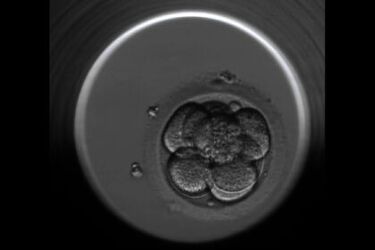

Fot: Klinika Leczenia Niepłodności "Bocian". Zdjęcie z Embrioskopu

Po umieszczeniu zapłodnionych komórek w embrioskopie urządzenie wykonuje zdjęcia poszczególnych oocytów, zygot oraz zarodków z częstotliwością ok. 15 minut. System jest nieustannie kontrolowany przez komputer, gdzie zbierane są pliki ze zdjęciami. Embriolog obserwuje jedynie film poklatkowy złożony z sekwencji obrazów w komputerze. Na podstawie analizy ocenia aktualne cechy i tempo rozwoju zarodka, dynamikę podziałów komórkowych oraz czas ich trwania. Zastosowanie tego typu obserwacji jest pomocne w każdym przypadku, ze szczególnym naciskiem na pary, u których zapładniana jest większa ilość komórek, a ich inkubacja trwa do 5 dób.